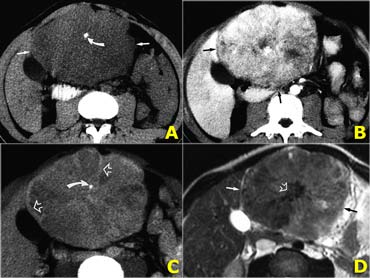

Left-lobe fibrolamellar HCC. Courtesy Dr. Federle and Dr. Ichikawa (3) Left-lobe fibrolamellar HCC. Courtesy Dr. Federle and Dr. Ichikawa (3)

Fibrolamellar HCC (3)

On the left CT- and MR-images of a left-lobe fibrolamellar HCC in a 19-year-old man.

A. Non-enhanced transverse CT scan shows calcification (curved arrow) within the hypoattenuating tumor (straight arrows).

B. Hepatic arterial contrast-enhanced transverse CT scan shows heterogeneous hypervascularity within the tumor (arrows).

C. Ten-minute delayed transverse CT scan demonstrates subtle areas of hyperattenuation that represent fibrous tissue within the central scar, radiating septa, and capsule (open arrows).

Curved arrow = calcification.

D. Transverse T2-weighted MR image (5,000/105) also demonstrates the central scar and septa (open arrow).

The tumor itself (straight arrows) is nearly isointense to liver (the only such case in our series).

On the left a photograph of the cut surface of the gross pathologic specimen shows a large tumor with eccentric and central scars (open arrows) and radiating septa.

The mass has an irregular lobulated pushing margin (solid arrows) and a variegated appearance with areas of bile staining.

In a series of 31 cases of FLHCC, Ichikawa et al (7) found the following:

• Large tumors (mean diameter, 13 cm) were depicted at CT and MR in all cases.

• At CT, the margins of the tumors were well defined in 24 (77%) of 31 cases.

• Calcifications were depicted in 21 (68%)

• Central scar in 22 (71%)

• Abdominal lymphadenopathy in 20 (65%).

• In 20 (80%) of 25 cases with hepatic arterial phase CT images, tumors were heterogeneous and depicted areas of hypervascularity.

• At MR imaging, tumors were hypointense to liver on TI-weighted images (n = 11) and hyperintense to liver on T2-weighted images (n = 10).

• Calcification was not depicted on MR images, but a central scar was depicted as hypointense to surrounding tumor in nine cases.